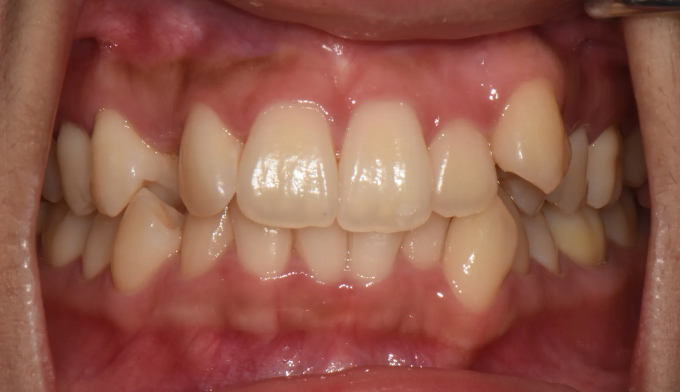

덧니,

돌출입

10대

2025.02.11